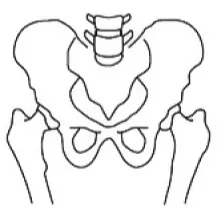

골반 엑스레이 검사 (risser sign) 검사로 성장 정도 파악

Risser 0

Risser 1

Risser 2

Risser 3

Risser 4

Risser 5